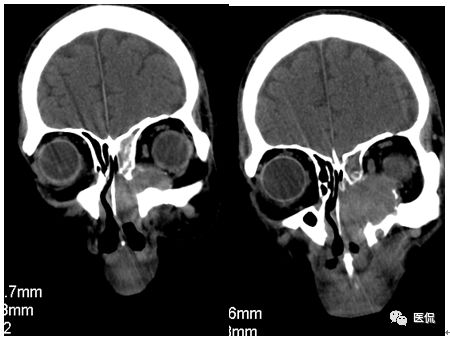

增强动脉期

CT平扫及增强示:左侧上颌窦及鼻腔可见软组织密度影,呈膨胀性生长,周围骨质压迫性吸收破坏,累及左眶,病灶密度不均匀,周边区可见点状钙化,增动脉期轻度强化,局部见小灶性稍高密度区,静脉期病灶内见不均匀明显强化,CT值最高达117HU,延迟期强化范围有所增大。

本例病灶较大,周围骨质可见吸收破坏,并累及眼眶,病灶内少量钙化,增强扫描具有一定特征性,表现为动脉期轻度强化,局部见小灶性稍高密度区,静脉期病灶局部呈明显强化,CT值最高达117HU,延迟期强化范围有所增大,呈延迟渐进性强化的特点,推测为病灶内出血所致。